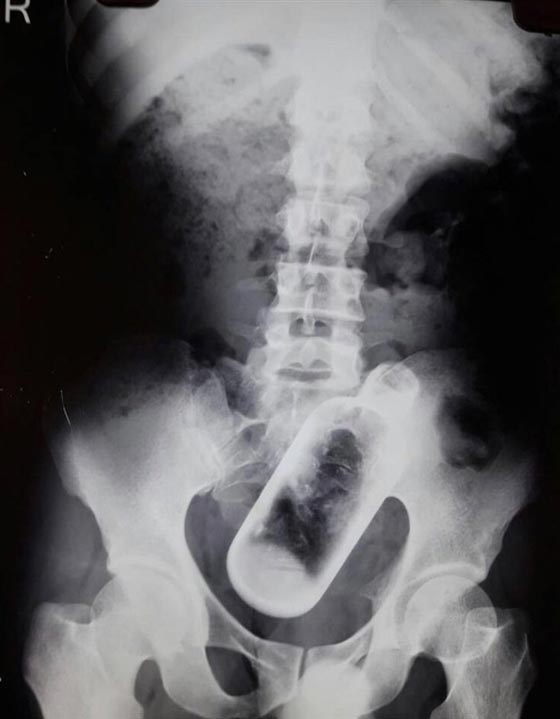

أصيب رجل هندي بالصدمة عندما أدرك أن معدته داخلها زجاجة طولها 16 سم. وذكر موقع اخباري أن الرجل البالغ من العمر 36 عاما، ذهب إلى المستشفى يشكو من آلام في المعدة وأسفل ظهره، وفوجئ الأطباء بالزجاجة داخل جسمه بعد إجراء فحص بالأشعة السينية. وقال السكان المحليون: إن الرجل ادعى أنه كان تحت تأثير الكحول، وربما وقع الحادث بالخطأ. واستغرق 4 جراحين نصف ساعة فقط لإزالة الزجاجة في معهد مهراجا أجراسن للبحوث الطبية والتعليمية في الهند.